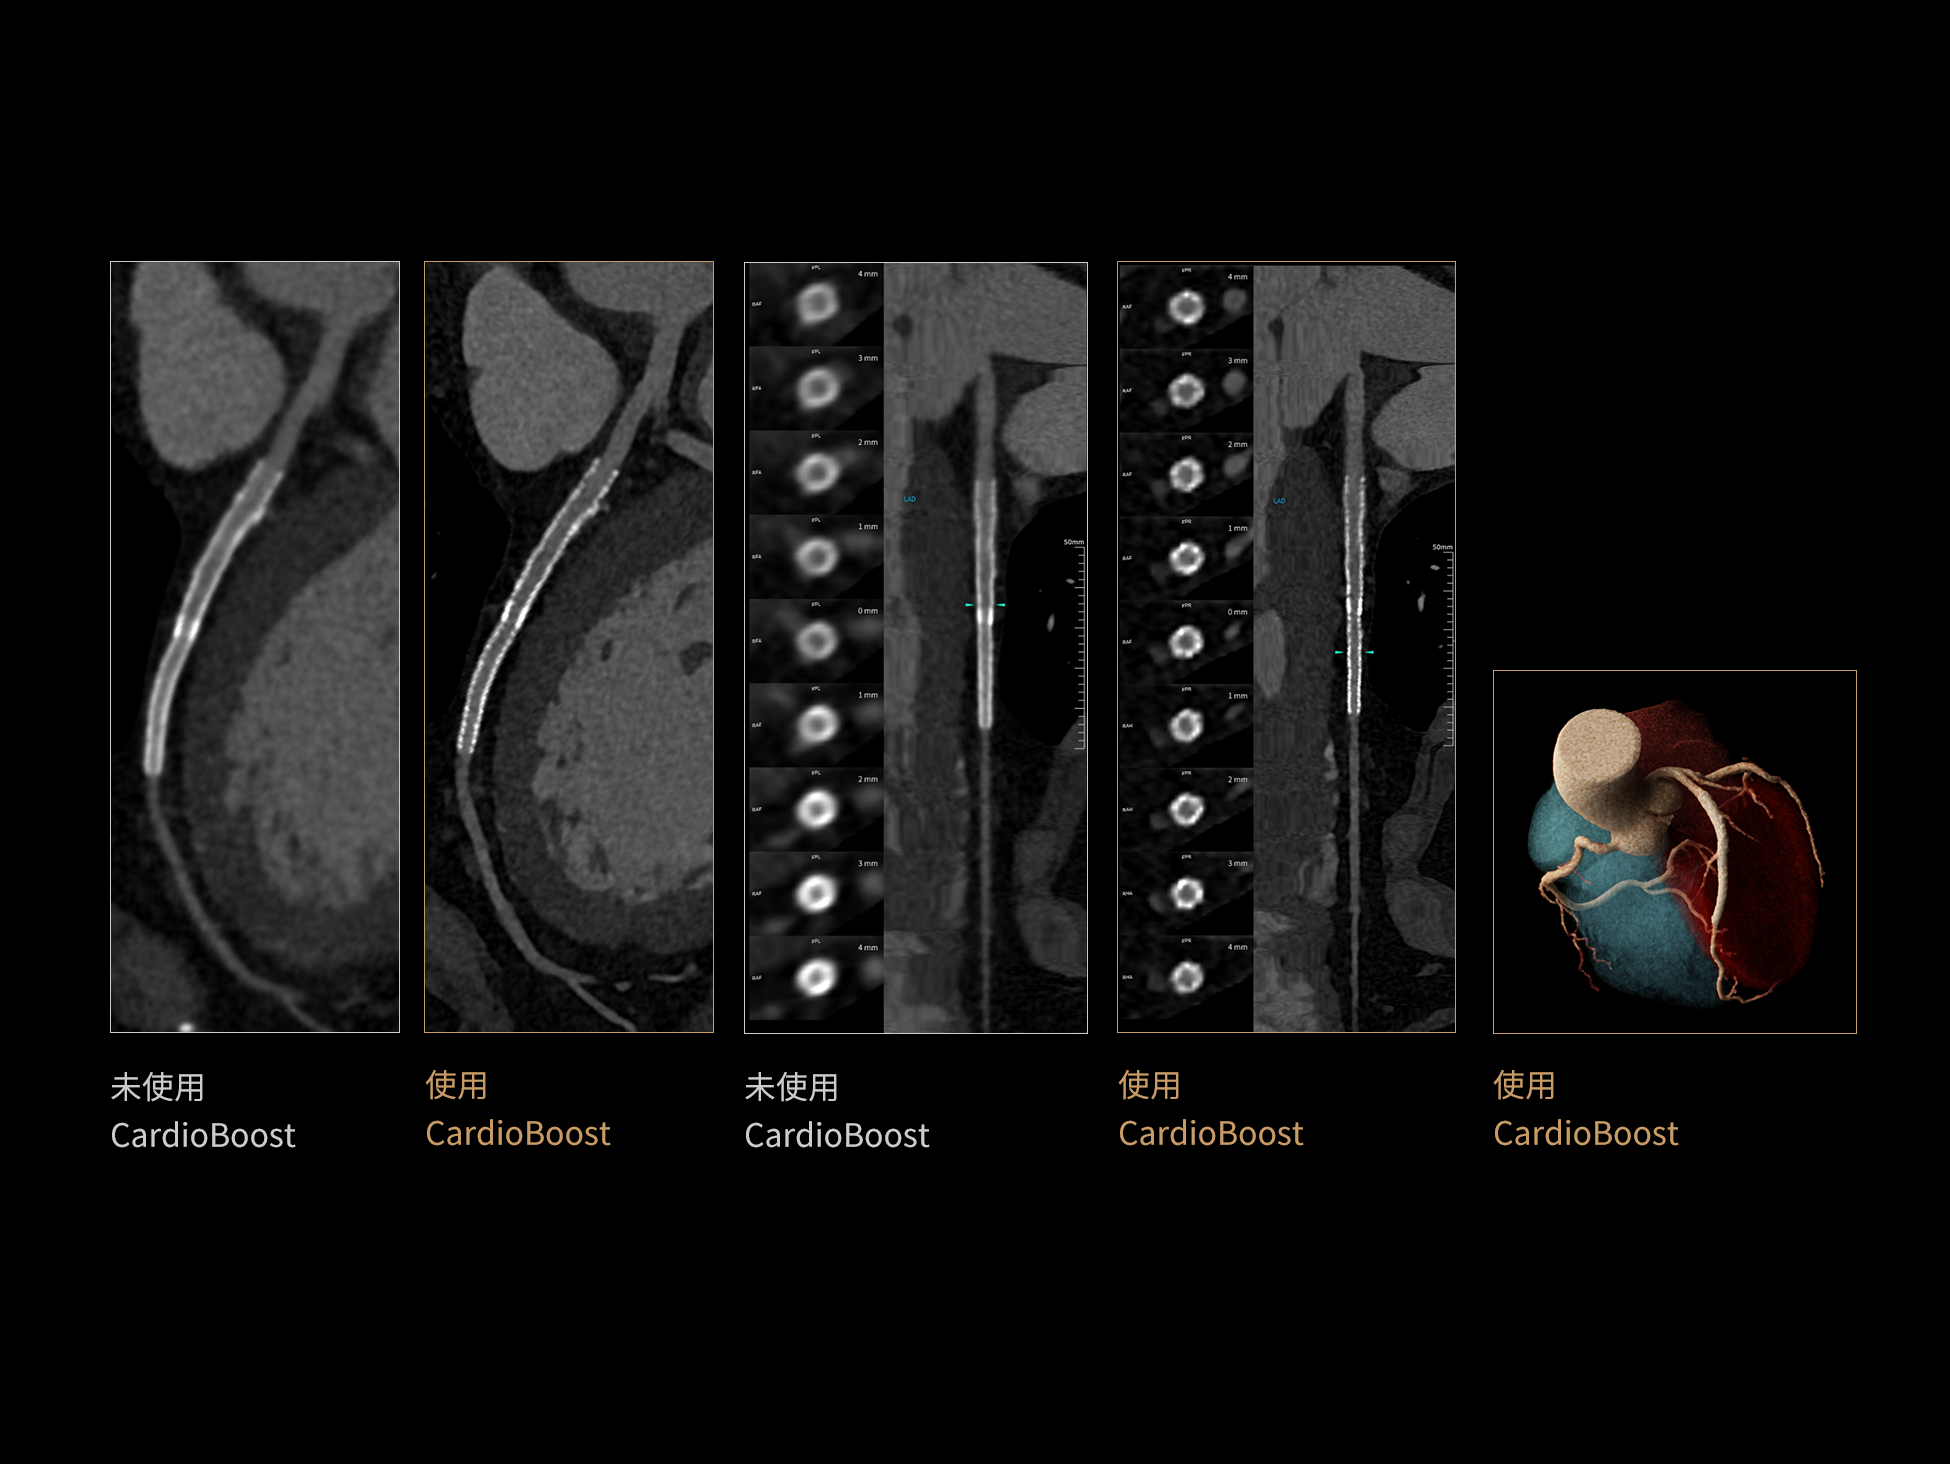

CardioBoost:专属网络设计,重塑心脏影像表现

目前心脏的 CT 检查还存在辐射剂量偏高、空间分辨率不足、 致密钙化伪影影响冠脉狭窄程度评估等方面的限 制[1][2]。CardioBoost 技术专为心脏 CT 高清成像而开发,通过 3D 神经网络的深度学习技术,利用先进的注意力机制在识别关键成像特征方面的出色表现,能够精确地聚焦于斑块、支架以及微小血管等关键细节,清晰展示这些结构与冠脉血管的边界,从而显著提高诊断的准确性,并提升医生的诊断信心。创新的 CardioBoost 心脏图像重建算法,不仅实现了图像清晰度的提升和伪影的去除,更能在减少辐射剂量的同时,保证心脏图像的高质量和图像纹理的自然。

采用 3D 神经网络的空间结构优势与精细的组织分类能力,CardioBoost 技术优化了组织对比,高清展示血管斑块,使斑块与血管边缘的轮廓清晰可辨,提升斑块诊断与评估的精确性。

借助 3D 神经网络设计、空间注意力机制聚焦与特征强化作用,CardioBoost技术提升图像的空间分辨率,实现冠脉支架的高清成像,对支架形态与管腔通畅度的评估更精准。

CardioBoost 整合先进的 3D 神经网络和空间注意力机制,大幅增强数据处理的速度与精确度。该技术能有效抑制由致密钙化引起的晕状伪影,清晰展现钙化斑块的原始结构和大小,对冠脉狭窄的评估更加精确可靠。

对比度强化模块

分辨率强化模块

伪影抑制模块